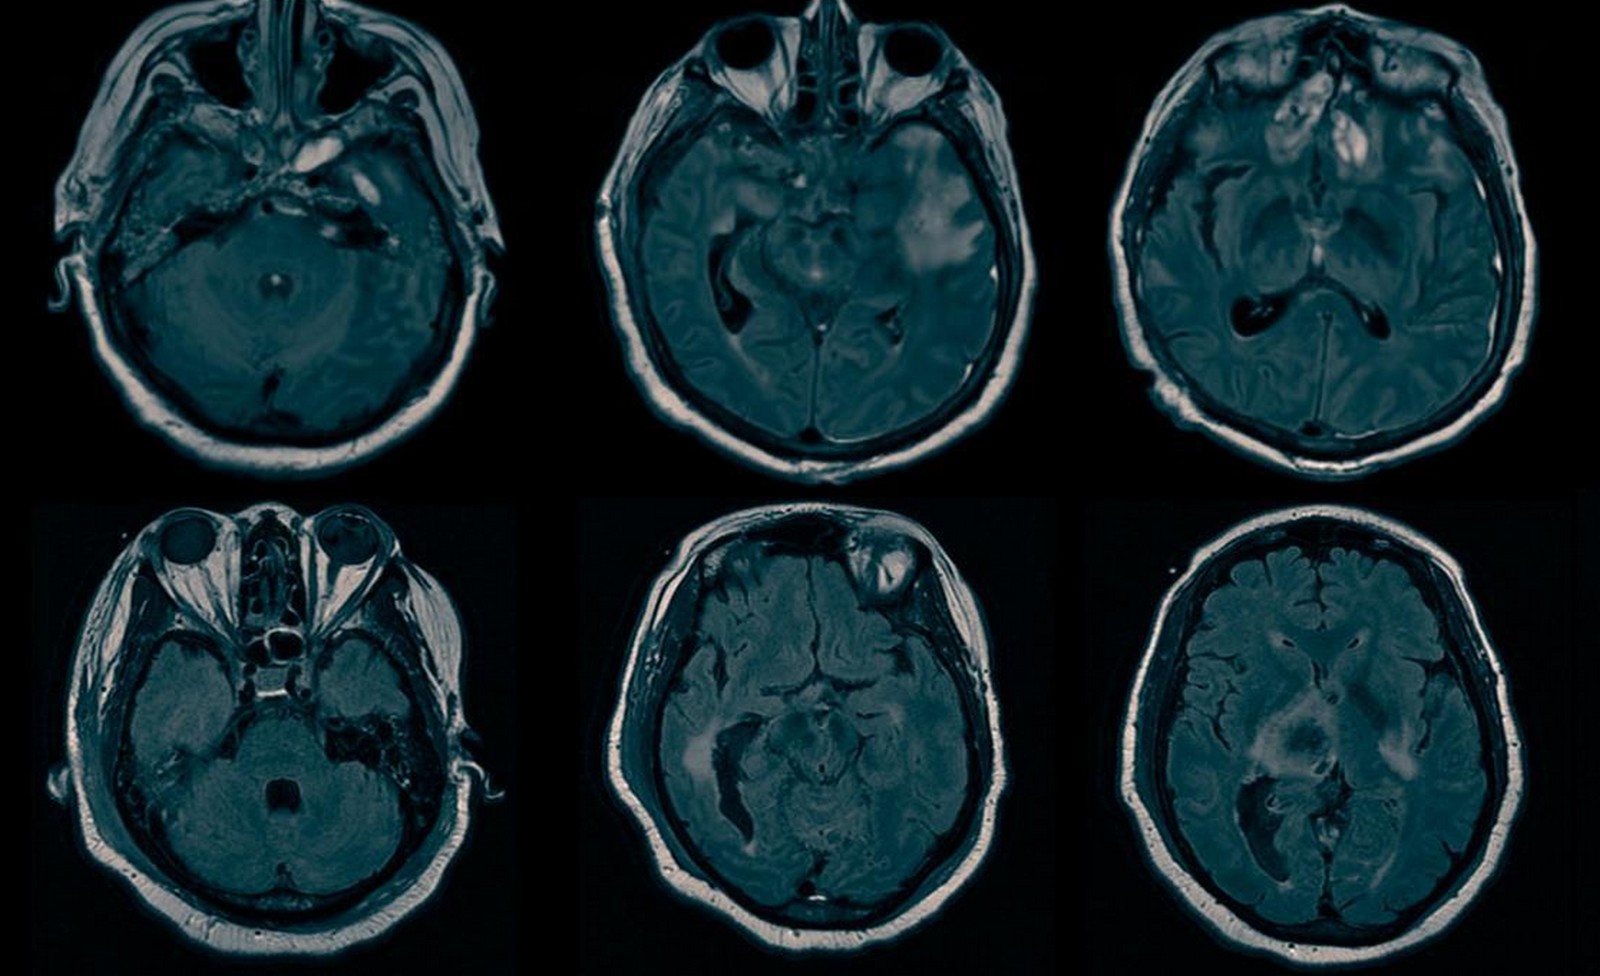

Σήμερα, εάν κάποιος φτάσει σε αίθουσα έκτακτης ανάγκης με εγκεφαλική κάκωση, το ιατρικό προσωπικό χρησιμοποιεί συχνά αξονικές τομογραφίες ή δομική μαγνητική τομογραφία, τεχνική που δημιουργεί εικόνες του εγκεφάλου ώστε να εντοπίσει προβλήματα που πρέπει να εντοπιστούν άμεσα -όπως είναι το οίδημα, οι διαρροές υγρών ή αιμορραγία.

Στην παρούσα φάση, η διάγνωση της κρυφής συνείδησης μπορεί να γίνει μόνο σε λίγα εργαστήρια σε όλον τον κόσμο. Εκεί χρησιμοποιούν το λειτουργικό ηλεκτροεγκεφαλογράφημα της πιο προηγμένης προσέγγισης από το παραδοσιακό ΗΕΓ, όπως και η λειτουργική μαγνητική τομογραφία (fMRI), που μετρά τις αλλαγές στη ροή του αίματος σε όλο τον εγκέφαλο.

Επέστρεψαν στο 0, άρχισαν να αναζητούν εγκεφαλικές βλάβες σε δομικές μαγνητικές τομογραφίες, μετά πρόσθεσαν τη δομική μαγνητική στην εξίσωση και έπειτα το ηλεκτροεγκεφαλογράφημα.

Στη συνέχεια, οι ερευνητές ανέλυσαν δομικές μαγνητικές τομογραφίες από όλους.